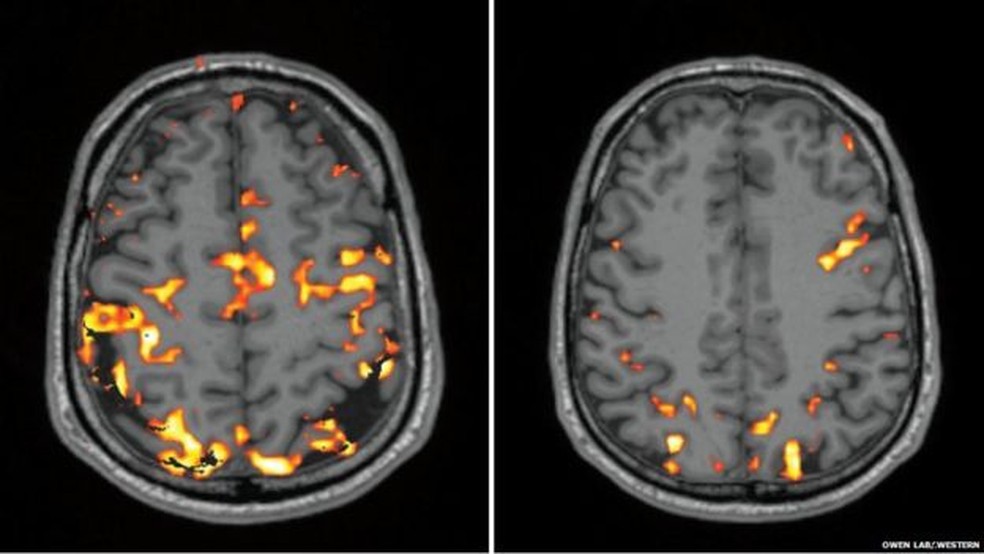

"Meu cérebro foi examinado duas vezes - depois de uma noite de sono normal e logo depois de uma noite mal dormida. A tomografia é capaz de detectar o fluxo de sangue no meu cérebro - as áreas que estão trabalhando mais intensamente são identificadas pelas manchas laranjas", explica.

Imagem à esquerda mostra atividade do cérebro do repórter durante testes cognitivos depois de uma noite de sono normal, enquanto a da direita, do seu cérebro privado de sono (Foto: Owen Lab, Western )

A comparação entre as duas imagens não deixou dúvidas: por causa da falta de sono, o cérebro do jornalista apresentou um nível de atividade bem baixa.

"Há muito menos atividade nos lobos frontal e parietais - áreas que sabemos serem cruciais para a tomada de decisões, a solução de problemas e a memória", explica Owen, o coordenador do estudo.